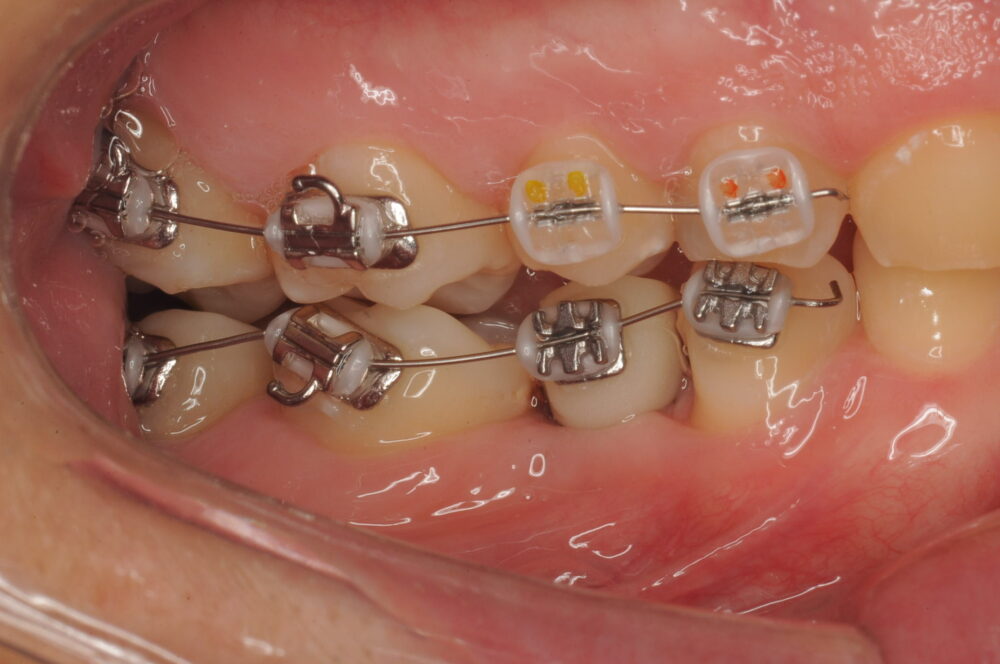

プロビジョナルレストレーション(暫間修復歯)作製のためのスキャンを行い、技工士にデジタルデザインを依頼したところ、左右対称のデザインを実現するには、一部矯正治療の追加が必要であると判断し、右上の奥歯(計8本)のみブラケット治療を行うことになりました。

ブラケット治療開始から8ヵ月、今回の治療目的が達成していることを確認し、再びアライナー治療を再開しました。